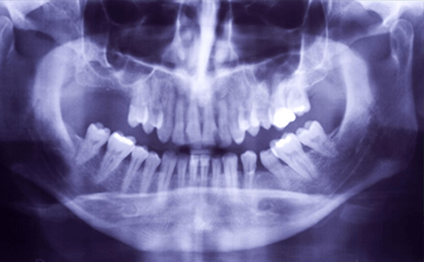

従来のレントゲンに比べ放射線量が1/10とお身体に優しいレントゲンです。

すぐにモニターで見る事ができ、お待たせしません。

レントゲン画像やお口の状態が確認でき、治療計画なども分かりやすく理解する事ができます。